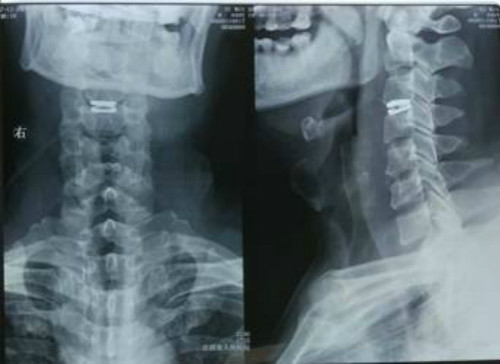

术前核磁共振显示C34椎间盘突出压迫脊髓致其变性

看到漂亮的术后X光片,体会到麻醉醒后立竿见影的手术效果,叶先生兴奋不已。就在进手术室前,电视台记者采访他时,他的左手还不能用力抓握,右手更是无法握拢,而术后一觉醒来,他两只手都可以握住甚至抓牢主刀医师董谢平的手了;术前的蹒跚步态也变得稳健了。晚上来看望他的家人走到近前发现站在走廊上与医生交谈的病人竟然是他们的亲人时,都惊喜得合不拢嘴来。